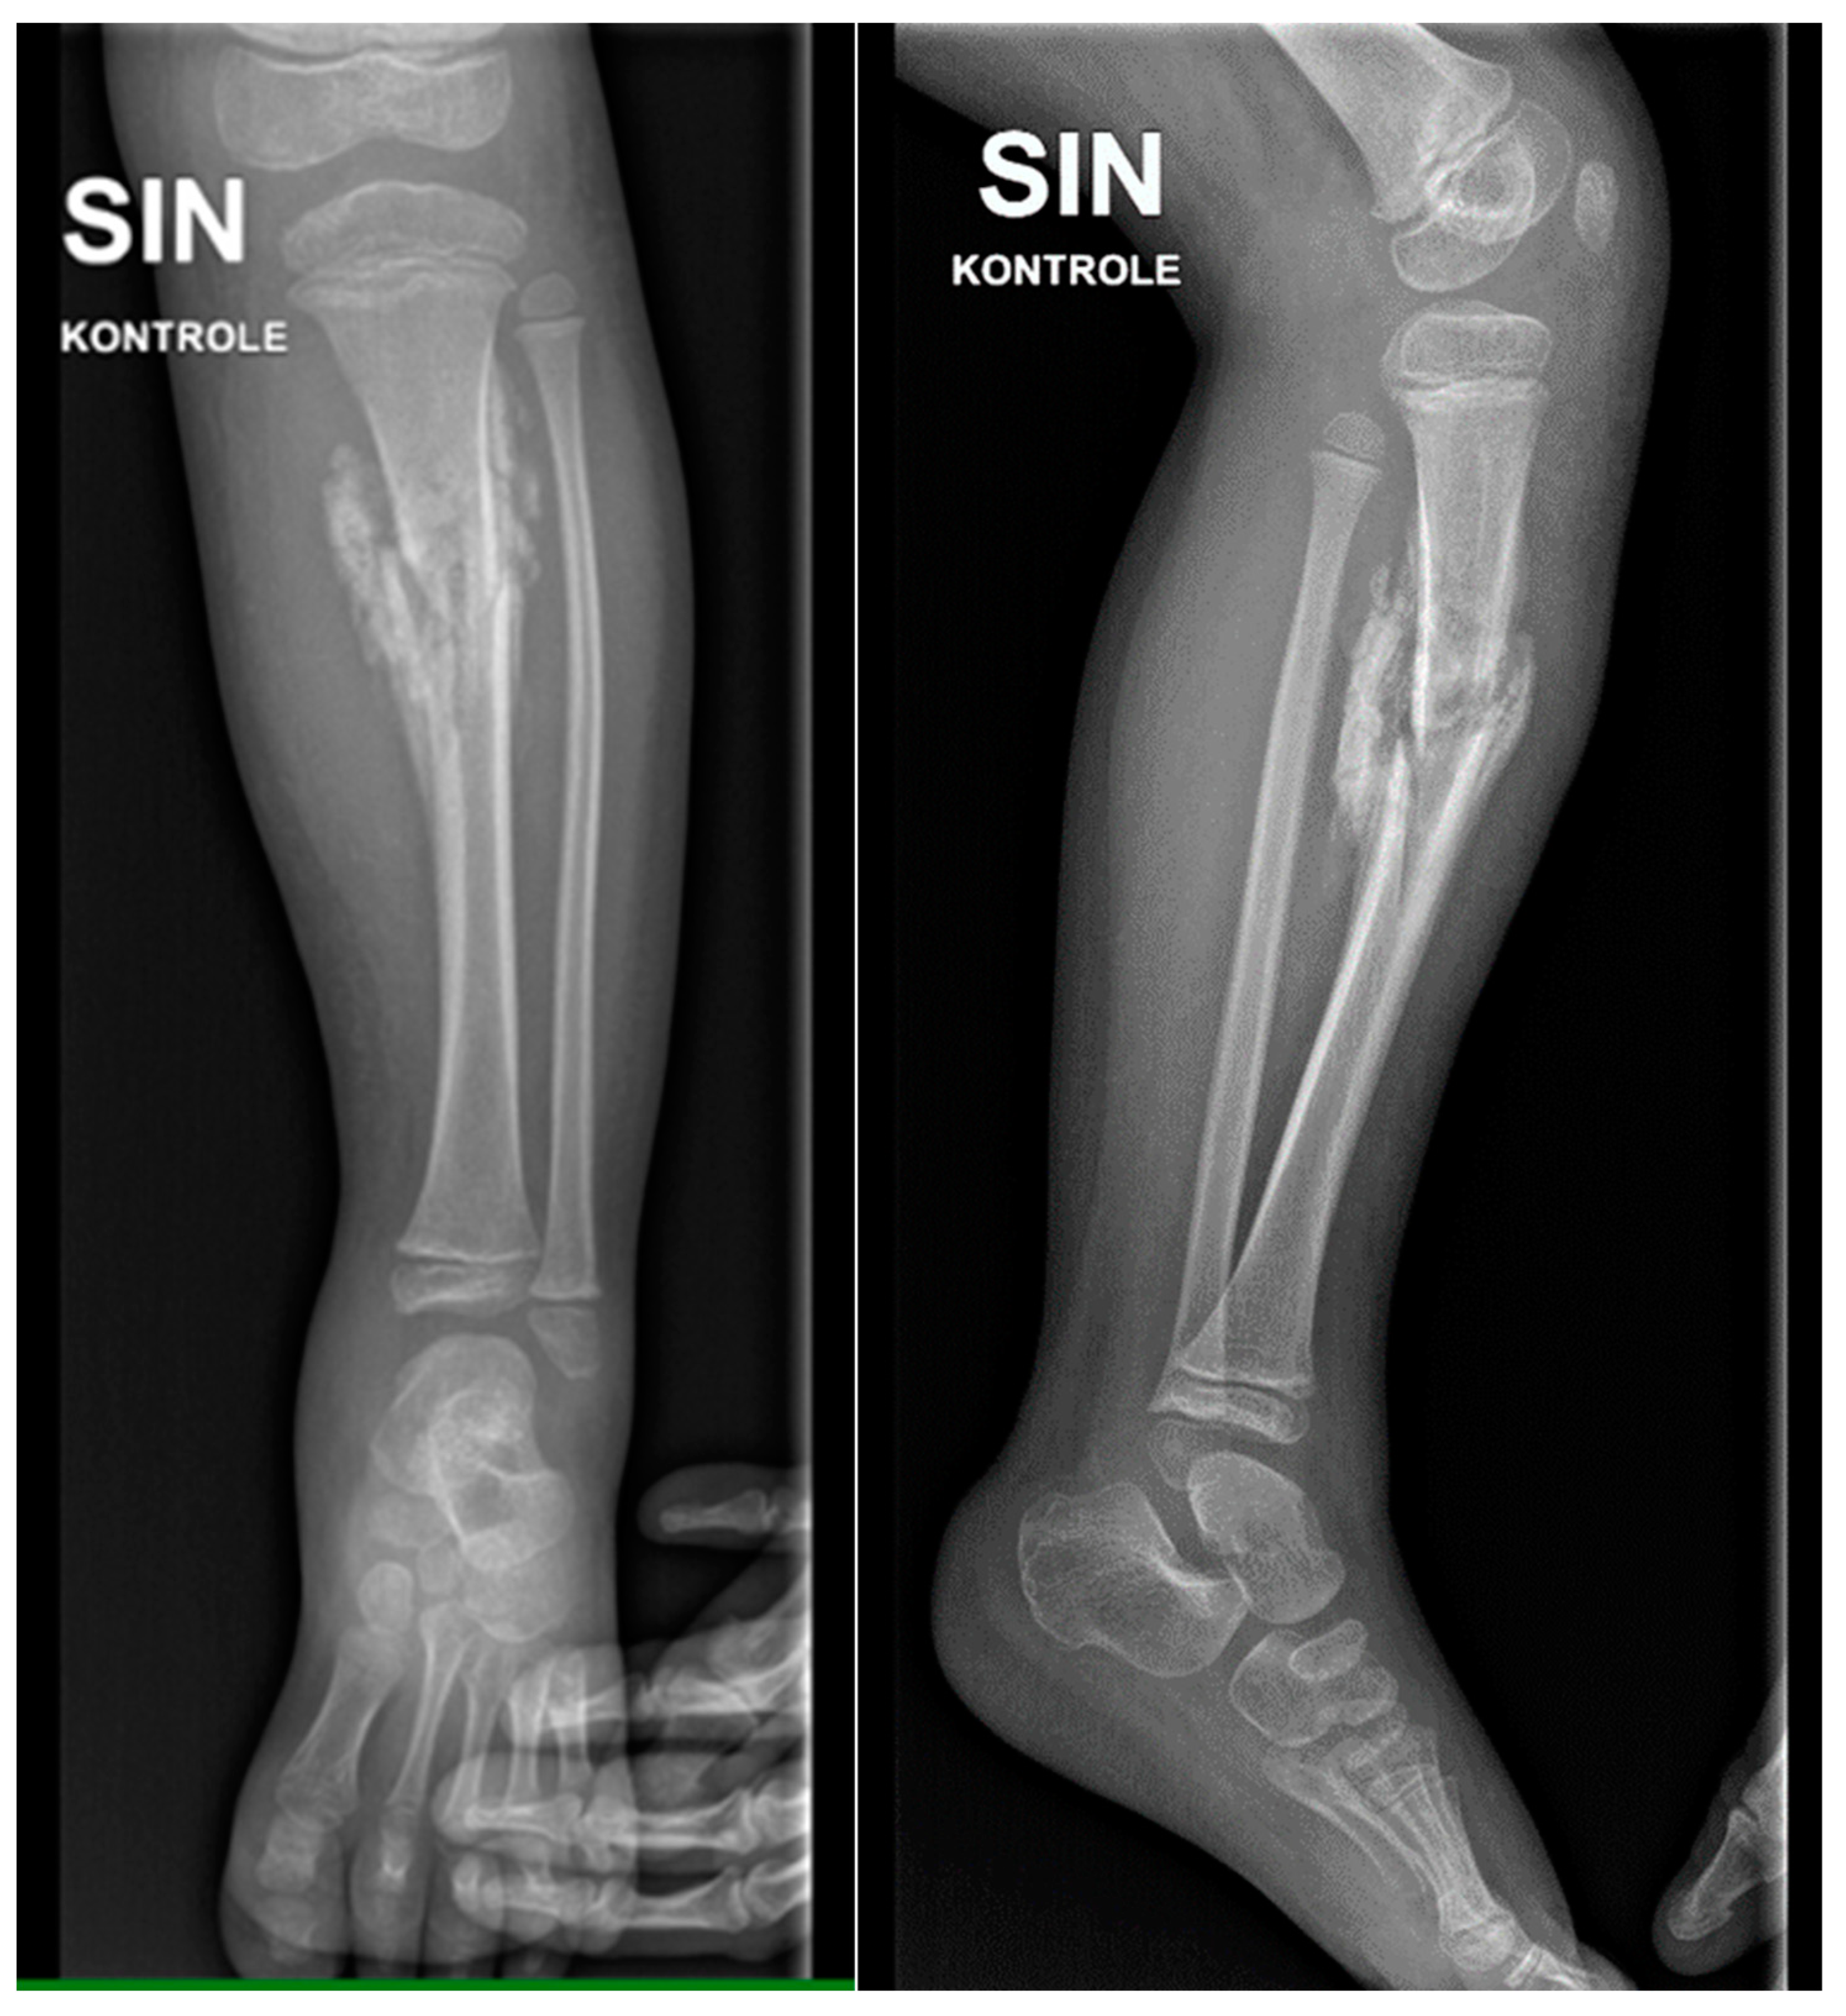

Figure 11. The X-ray examination of the distal third of the thigh in AP and lateral projections shows a condition after posttraumatic chronic osteomyelitis of the left tibial diaphysis. For the left thigh - the picture corresponds to the condition after an epiphyseal fracture in the anamnesis, the lateral condyle of the femur is of small volume, heterogeneous structure. Massive calcification paraosseous to diaphysis of femur.

Figure 12. X-ray examination of the proximal part of the left foot and the distal third of the lower leg in AP and lateral projections shows a condition in the left foot and lower leg after a plate fixation and implantation of a resected fibula diaphysis fragment. The area is not fully covered, and intense humming has developed after distal tibial osteoepiphysiolysis. Slight deformation in the metaphysis of the fibula remnant is also present.

Figure 13. X-ray examination of the left foot in AP and lateral projections. A fracture of the distal metaphysis of the second metatarsal bone of the left foot is visible without dislocation.